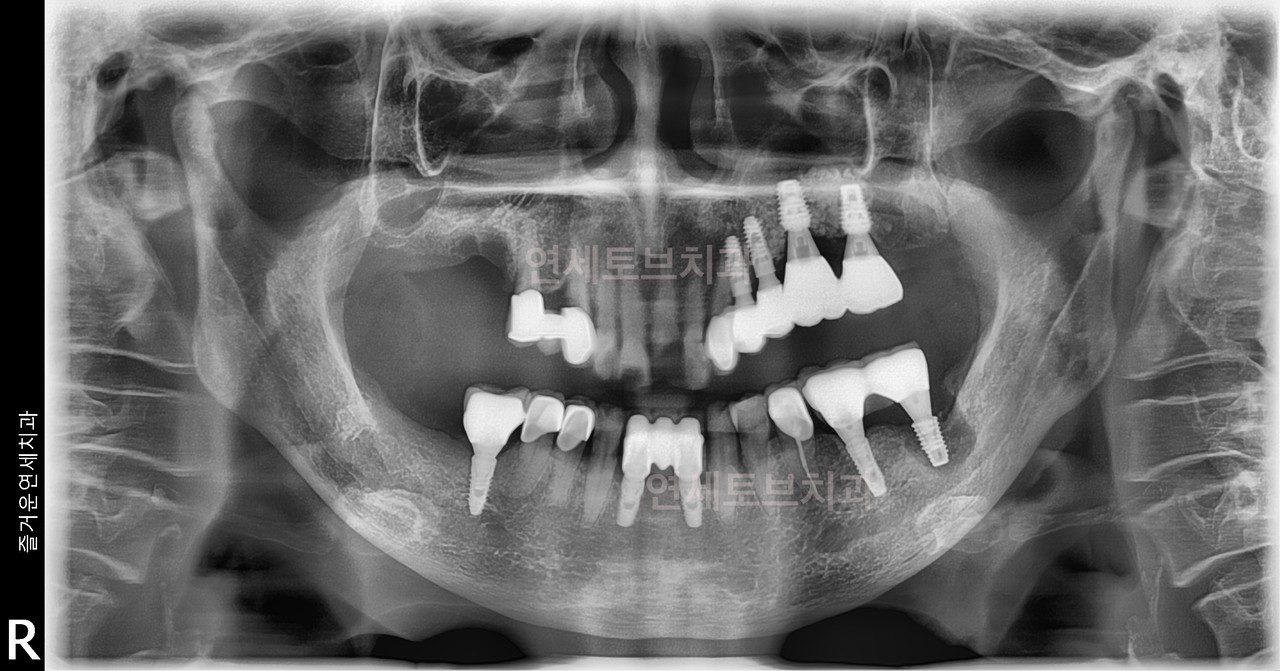

#1

#2

#3

#4